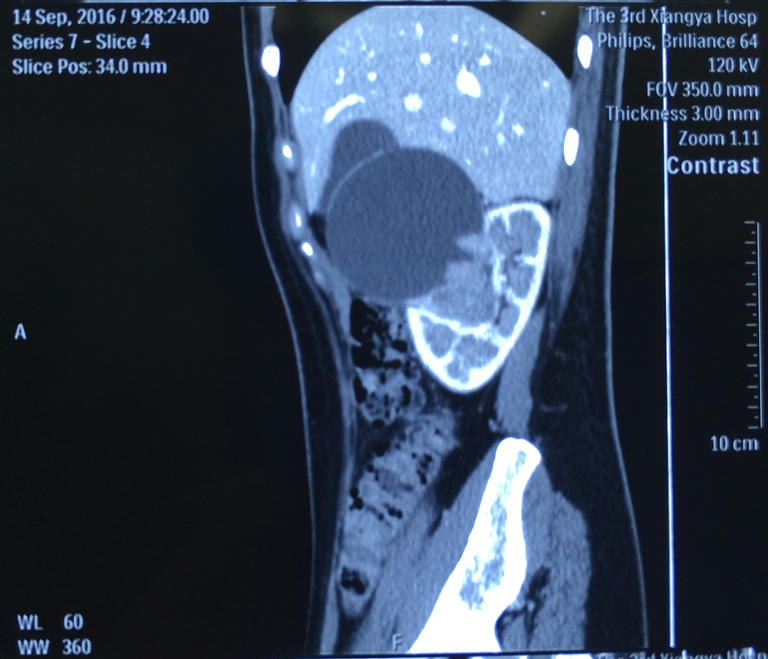

肾脏部分切除即只切除肾肿瘤而保留正常肾脏,但这一治疗方案要求医生对个体肾脏解剖结构有极高的了解。为了从普通双肾CT片中了解更多更直观的信息,医生通过将双肾CT的信息输入电脑中,利用3D打印技术精准复制该患者的肾脏结构并打印了患者的肾脏模型。术前医生即可清晰地看到肿瘤的位置、肾脏血管的分支及走行的方向等解剖结构。

利用3D打印技术精准复制患者的肾脏结构并打印模型